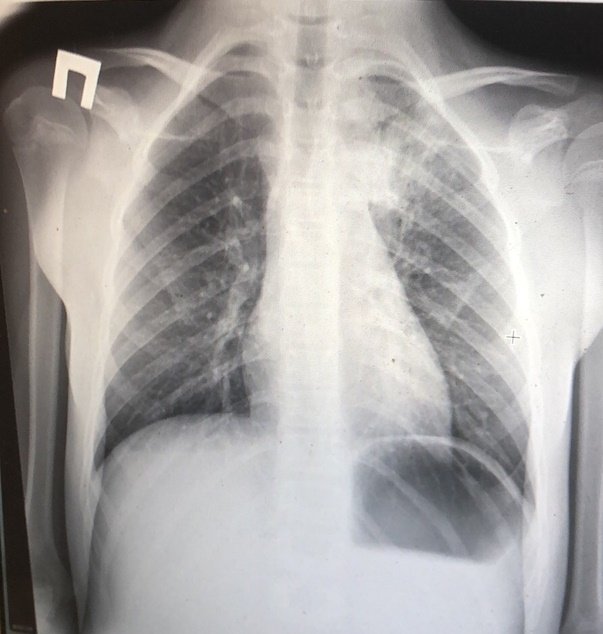

При абсцедирующей пневмонии на снимке отчетливо видно тотальное затемнение области инфильтрации и уплотнение плевры; наблюдаются полости до 2 см, в которых скапливается гнойная жидкость.

Фотоснимок при абсцедирующей пневмонии